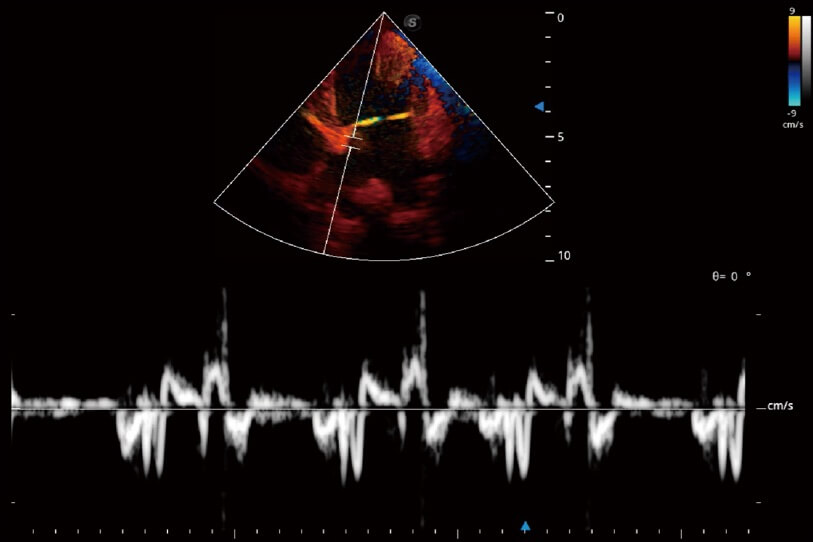

實(shí)時(shí)用顏色表示心肌組織運(yùn)動,觀察和定量組織的運(yùn)動情況,對快速檢測與評估心肌的灌注和活性、電傳導(dǎo)及心肌收縮和舒張功能等均能提供重要的診斷信息。

通過360度任意調(diào)節(jié)3條M型取樣線,在同一心動周期上觀察心臟不同位置的運(yùn)動曲線,得到準(zhǔn)確的心功能測量數(shù)據(jù),有效評估心肌運(yùn)動及左心室功能。

通過創(chuàng)新的 Matrix E自適應(yīng)濾波器和超長時(shí)間域算法,極大提升超低速微細(xì)血流的檢出能力,同時(shí)更精準(zhǔn)地濾除軟組織和噪聲信號,為獸用醫(yī)生提供以往無法通過常規(guī)血流獲得的疾病診斷信息。